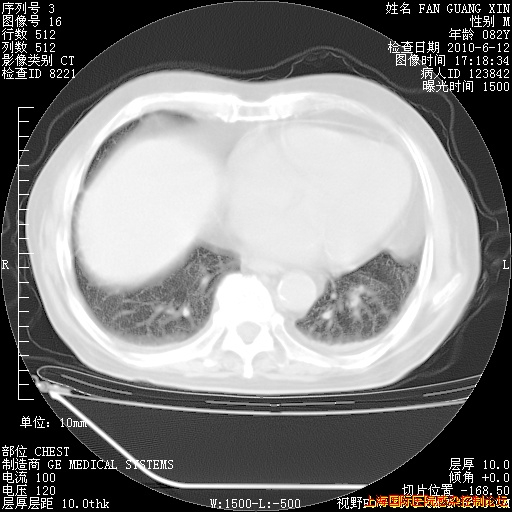

补发6月12日肺部CT肺窗

6月12日肺窗

整整相隔30天的肺部CT好像有所好转啊。甲强龙减量第3天,需要观察体温。